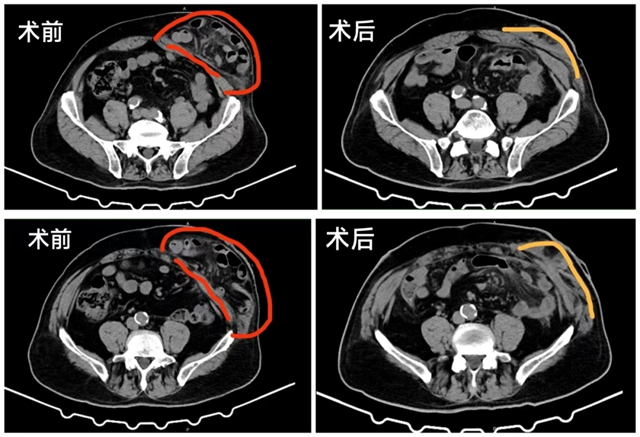

经过充分的术前评估,郭伍斌副教授带领罗伟主治医师、刘飞主治医师等手术团队,为黄大爷实施了腹腔镜下造口旁疝无张力修补术。术中,医生们发现存在腹腔多处粘连,大量小肠及网膜从造口旁疝出并伴有粘连,缺损面积达6*5cm,手术难度陡增。

好在经过3个小时的紧张手术,郭伍斌副教授手术团队顺利完成了手术。黄大爷术后恢复良好,造口下方的大包消失了,便秘及造口脱垂也明显缓解。

因为有造口存在,手术难度较高,目前临床以腹腔镜下造口旁疝无张力修补术为主,相比开放手术,其具有创伤小、恢复快、复发率低的优势。

当然其难度也是显而易见的,首先,疝囊位于造口周围,解剖结构复杂(涉及肠管、造口肠管肠系膜血管);其次,患者多有腹部手术史,腹腔粘连严重,术中需精准分离,避免损伤脏器,同时需确保补片位置合适、固定牢固,避免补片移位或侵蚀周围组织。最后,手术需要确保造口旁疝尽可能不复发的同时,造口功能不受影响,必要时还需重新造口。